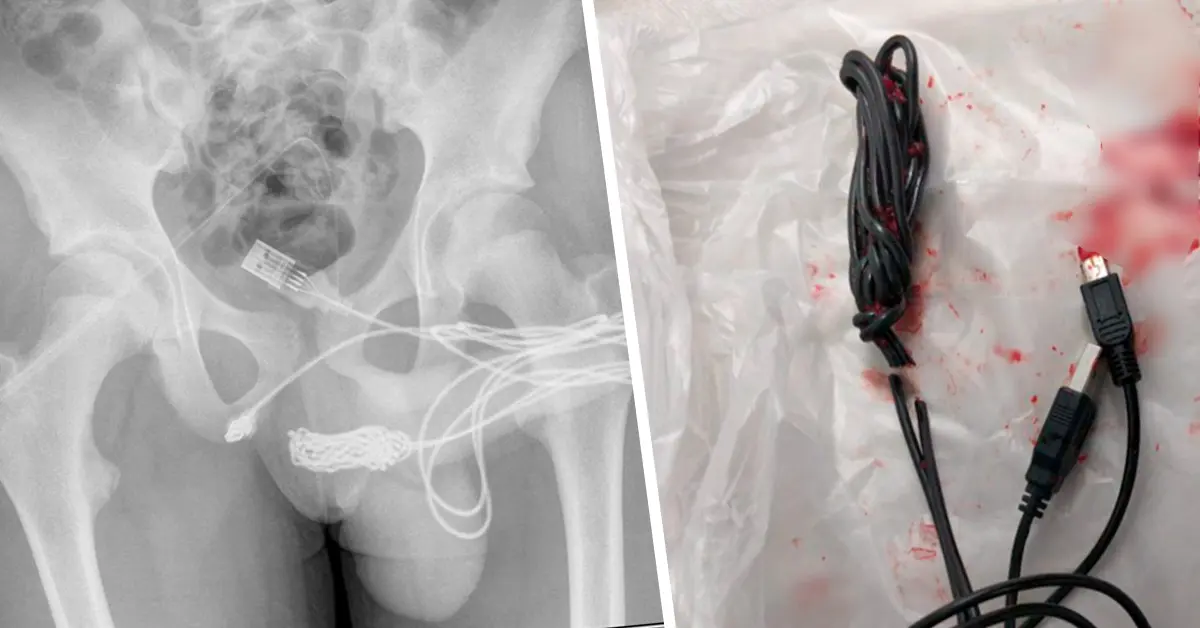

วันที่ 17 กันยายน 2564 สำนักข่าวต่างประเทศ รายงานว่า เด็กหนุ่มชาวอังกฤษวัย 15 ปี ที่ขี้สงสัยของเขาทำให้ต้องลำบากถึงคุณหมอ หลังจากที่เขาสอดสาย USB เข้าไปในอวัยวะเพศของตัวเอง เรื่องนี้ถูกเปิดเผยใน Urology Case Reports ซึ่งเป็นวารสารการแพทย์ โดยเด็กชายนำสาย USB เข้าไปในอวัยวะเพศ ซึ่งได้นำส่วนที่เป็นก้อนปมยัดเข้าไปทางรูอวัยวะเพศจนเกิดการอักเสบและฉี่เป็นเลือด

เนื่องจากสายเข้าไปติดอยู่ภายในท่อปัสสาวะ โดยมีส่วนหัว USB ทั้ง2 ฝั่ง ห้อยออกมาภายนอก ซึ่งเด็กหนุ่มได้พยายามจะดึงออกเองอยู่หลายครั้งแต่ก็ไม่สำเร็จ จนในที่สุดทางครอบครัวก็ช่วยกันนำตัวเขาส่งไปยังโรงพยาบาลท้องถิ่นแต่ ทางโรงพยาบาลไม่สามารถทำการรักษาได้เนื่องจากการกระทำดังกล่าวส่งผลทำให้เกิดภาวะโลหิตจาง จึงส่งตัวเด็กหนุ่ม ไปยัง University College Hospital London เพื่อทำการผ่าตัดด่วน

ภายหลังการผ่าตัดแพทย์ได้มีการสอบถามถึงแรงจูงใจในการกระทำนี้เพื่อตรวจสอบสภาวะทางจิตของเด็ก โดยเด็กหนุ่มได้ร้องขอว่าขอคุยกับหมอเพียงลำพังเท่านั้น โดยให้แม่ของเขาออกไปจากห้อง และได้เล่าว่าที่ทำลงไปเพียงต้องการที่จะอยากรู้ขนาดความใหญ่ยาวของตัวเองว่ามีมากขนาดไหน ทั้งนี้เด็กหนุ่มก็ยังต้องคงเข้ามารับการตรวจอย่างต่อเนื่องเพื่อดูผลข้างเคียงระยะยาวอันเกิดมาจากความขี้สงสัยของตนเอง